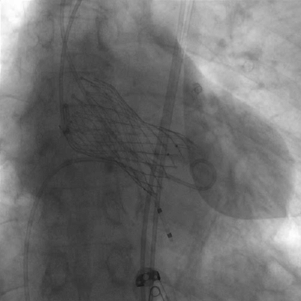

患者麻醉方式采取全麻,建立静脉通路后,穿刺左侧股动脉,建立副入路。在超声引导下精准穿刺右股动脉及股静脉,预埋两把ProGlide缝合器,置入20F动脉鞘管,漂浮电极经股静脉送至右室心尖。跨瓣成功后,将Lunderquist导丝送入左心室, 23mm球囊预扩张,Venus-A 29瓣膜精准定位并释放,术中造影及超声反馈良好,瓣膜形态良好,结果满意。

瓣中瓣释放

释放后造影结果

患者即刻跨瓣压差显著下降,再行主动脉造影提示瓣膜置入位置良好、形态完整,未见瓣周漏,未出现相关并发症,取得了良好的手术结果。